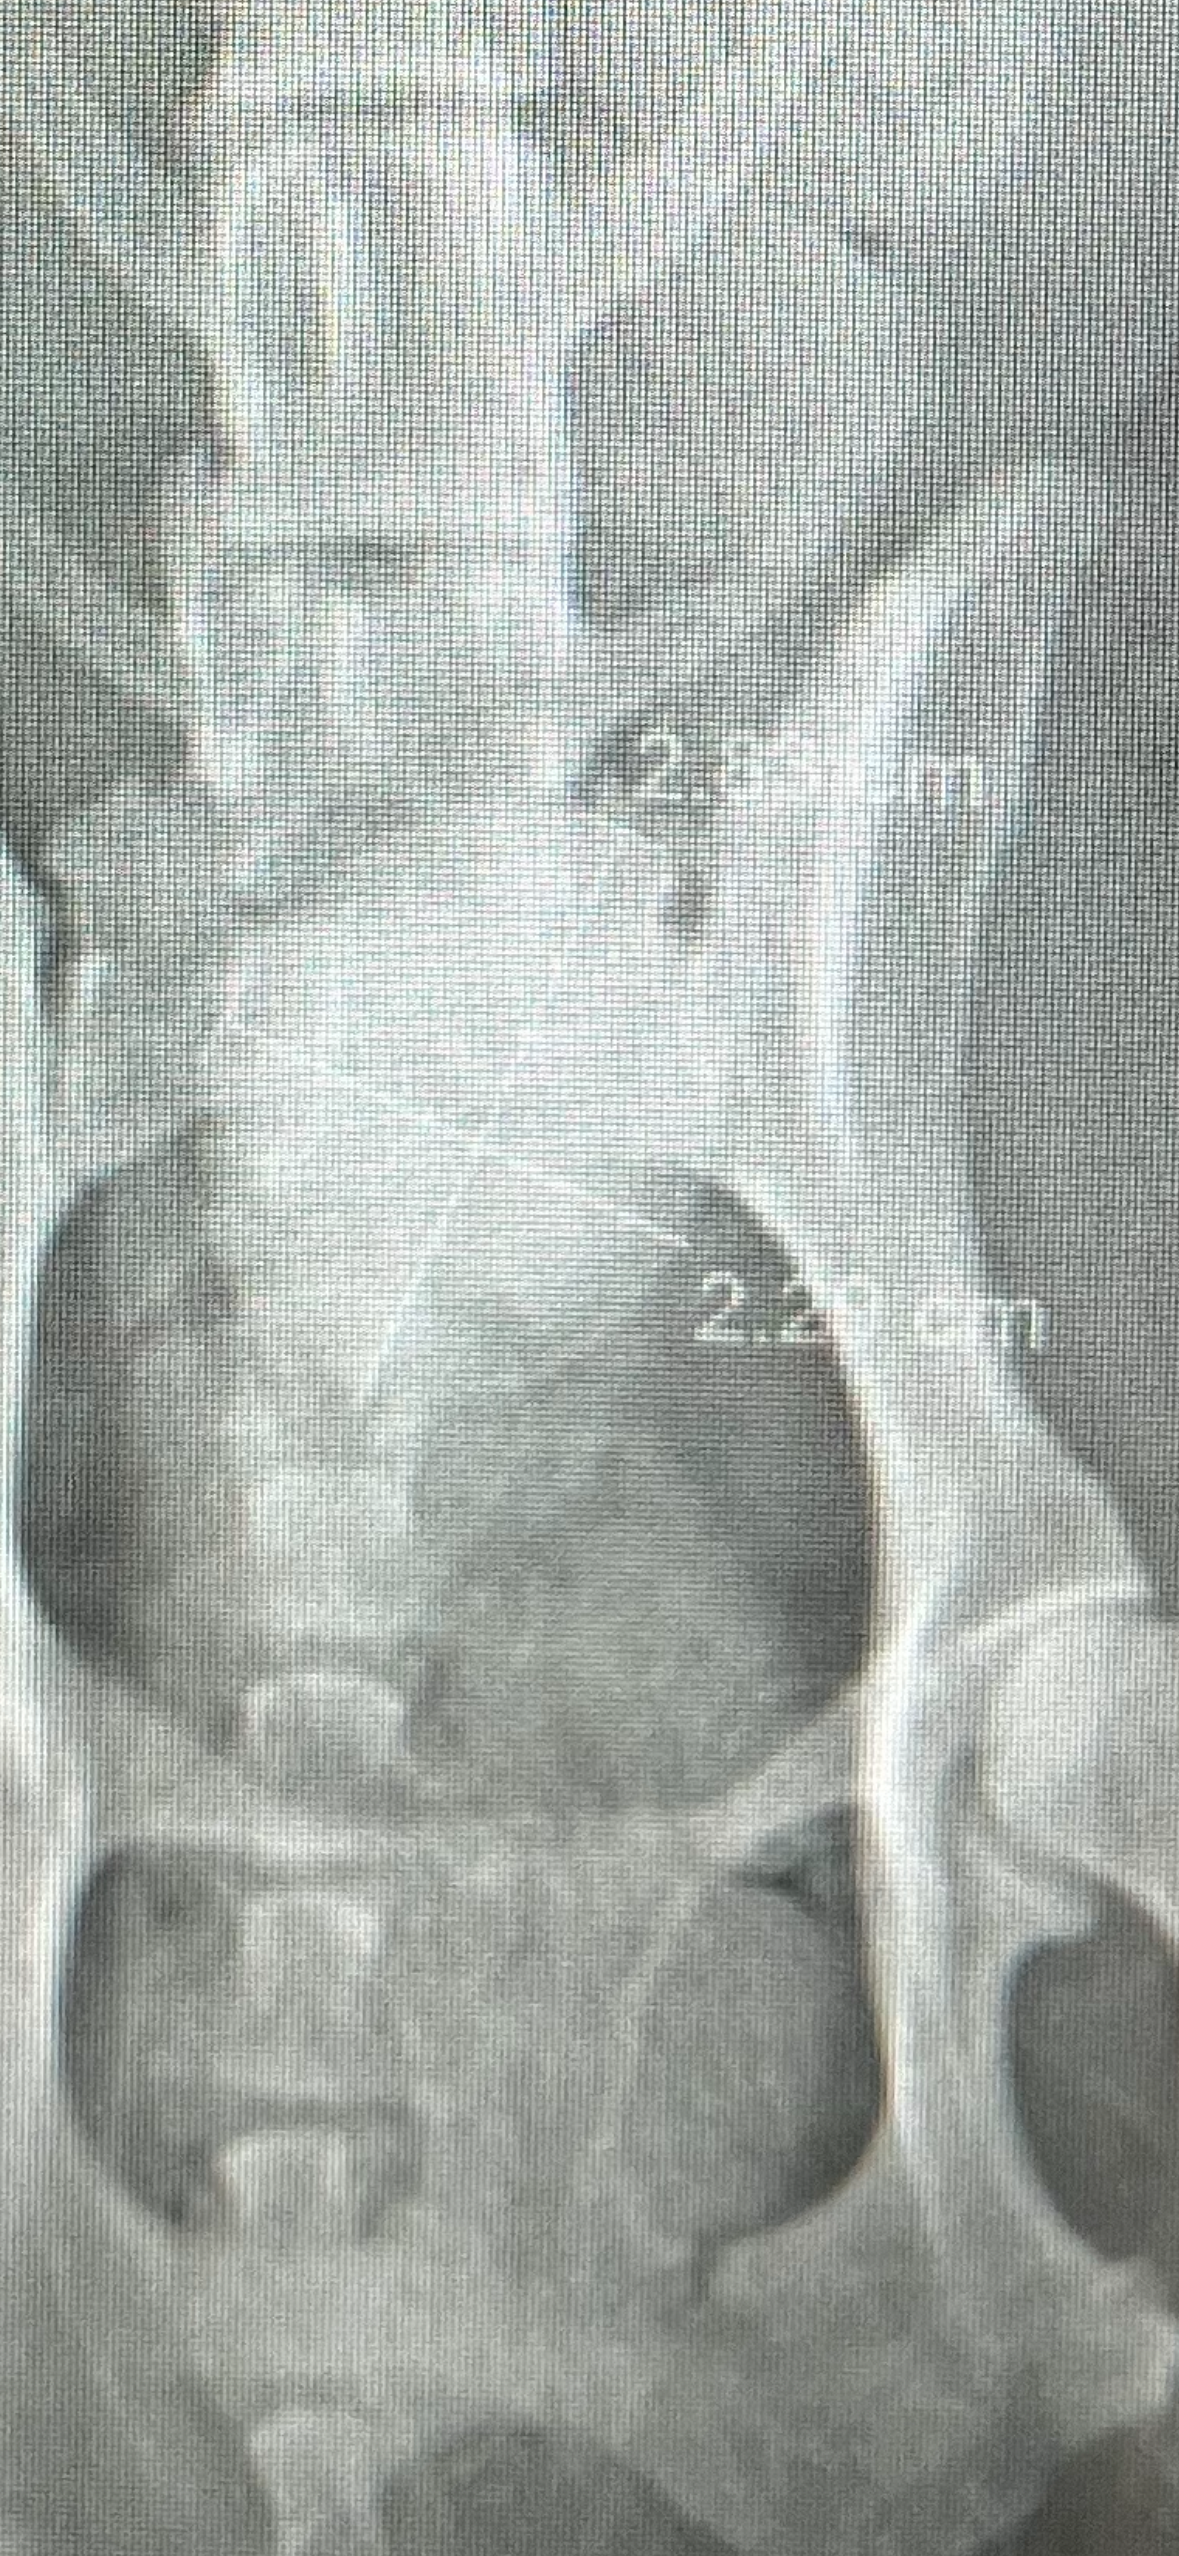

I adopted Keelah when she was just 6 months old, and now, at 16 years old, she’s still going strong. She was my first animal and my closest friend, bringing so much joy and comfort into my life. I can’t imagine my days without her by my side. Recently (3.20.26), she was diagnosed with a massive bladder stone, and it’s been heartbreaking to see her in pain.